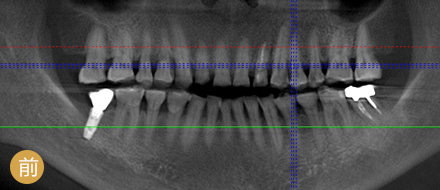

VS 传统种植牙 全数字化精确种牙

手术时间 平均1颗牙1小时 单颗牙5~10分钟

恢复周期 拔牙后3个月修养,需二次种植 即拔即种,即种即用

准确程度 依赖医生个人判断种植角度 外科导航系统定位,实时监控,避开血管神经

安全性 医生个人经验决定了种牙效果 神经、血管可见,导航全程定位,

种牙效果稳定可靠

功能行使 愈合周期略久,较难参与日常咀嚼 种牙后即可马上使用

操作医生 普通种植医生 麦芽博士级专家团队

手术创伤 一般要翻瓣缝合,不适感较强

体质差的人易感染与红肿

3毫米创口,精确植入牙骨

不翻瓣不缝合,术后基本无肿胀期